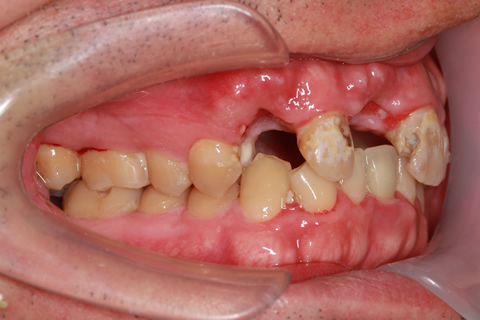

症例3

治療前

インプラント埋入時

治療後

- 年齢・性別

- 60歳男性

- 治療期間

- 2ヶ月

- 抜歯

- なし

- 治療費

- 61.6万円

- 備考

- 右下6.7欠損

- 治療内容

- 右下6.7欠損部にインプラント埋入

- 施術の副作用(リスク)

- オペによる知覚障害。インプラントによる歯肉炎。インプラント脱落。